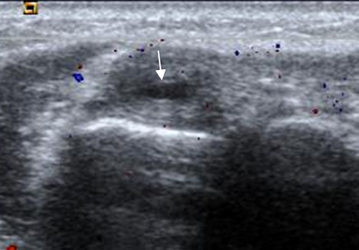

Fig 49 C. Epicondilitis lateral.

Ecografía. Engrosamiento sobre el origen común de los tendones,en el epicóndilo lateral, sin aumento de la vascularización con el estudio doppler. Hay area anecoica intrasustancia, por ruptura parcial.